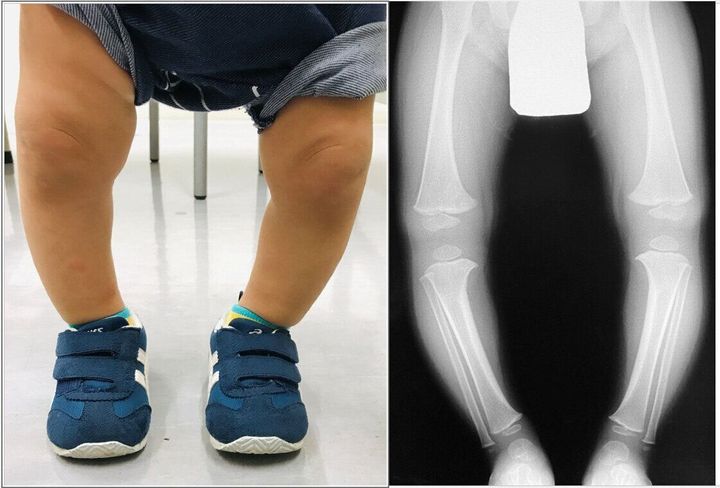

ほうっておいては治らない子も!乳幼児のO脚、産まれた環境にも原因が 専門家 たまひよ。

赤ちゃん股関節「脱臼してるかも」 痛みもなく元気に動くのになぜ。

クリニックブログ上高田ちば整形外科・小児科。